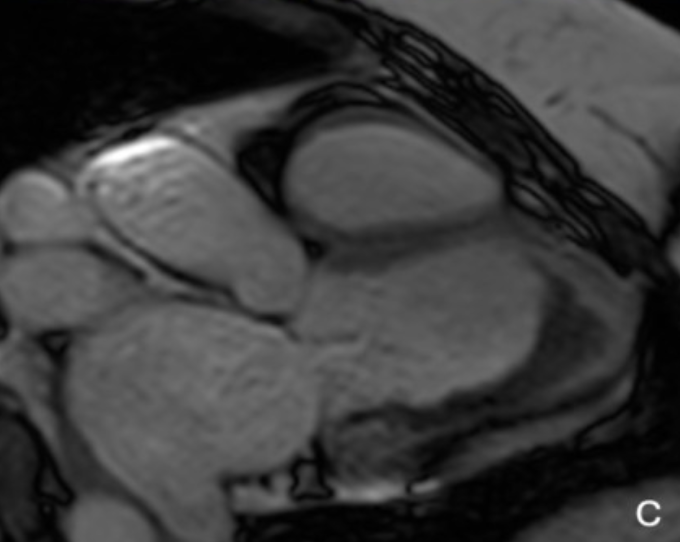

filling of the apical cavity of the left ventricle with fibrotic tissue, causing its obliteration

Subendocardial LGE with "V" morphology